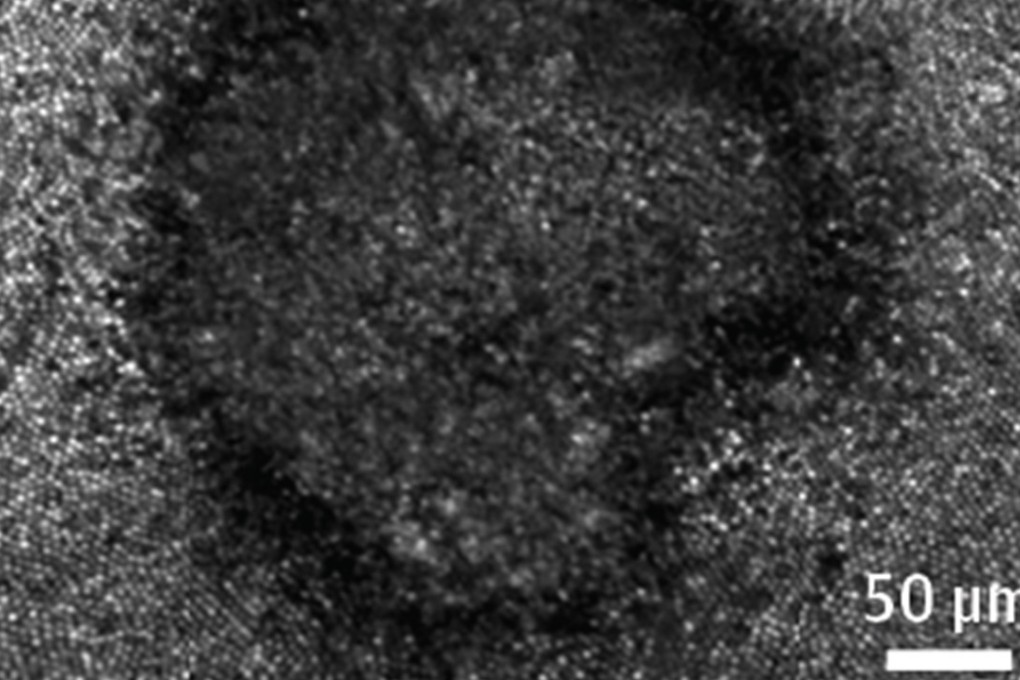

An eclipse-shaped image was burned onto the retina of a New York woman in her 20s who stared at the August 21 phenomenon without good eye protection. A retina scan revealed the dark grey circle in the shape of the sun with the moon's silhouette crossing its edge at lower right. Photo: JAMA

Advanced retina scans, performed at New York Eye and Ear Infirmary of Mount Sinai, revealed damage in the shape of the sun with the silhouette of the moon crossing its outer edge, study authors said. The woman described a corresponding “hole” in the centre of her vision, sketching a similar shape that looked like a cookie with a bite out of it.